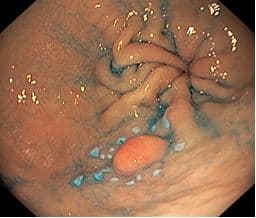

При гастроскопии перед оперативным лечением в нижней трети тела желудка по задней стенке (на границе с большой кривизной) было выявлено эпителиальное новообразование 0-IIa типа размером ~ 15 мм

На рисунке: Осмотр в белом свете. Эндоскоп: GIF Q-150 OLYMPUS. EXERA III. Эпителиальное новообразование 0-IIa типа размером ~ 15 мм.